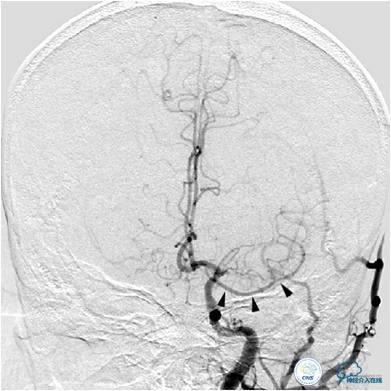

患者入院后,完善颅内CTA(图1)及血管造影(图2~3)检查,发现右侧颈内动脉颅内段闭塞,右侧大脑前动脉依靠左侧颈内动脉系统通过前交通动脉供血,右侧大脑中动脉供血区则依赖于右侧大脑前动脉(ACA)软脑膜代偿供血,左侧大脑中动脉闭塞,依靠一少见血管代偿供血,该血管起自左侧大脑前动脉A2段起始部,代偿供应左侧大脑中动脉供血区。由于该患者灌注CT(图4)未见明显低灌注区,遂给予患者抗血小板、降脂及控制危险因素治疗出院。出院后电话随访未再出现过上述症状。

图3A:左侧颈总动脉造影动脉期,看到异常血管代偿供应左侧大脑中动脉分布区(箭头),双侧大脑前动脉双干显示。

图3B:左侧颈内动脉造影动脉晚期提示双侧大脑半球染色尚可,右侧大脑中动脉供血区由右侧大脑前动脉的软脑膜动脉代偿。